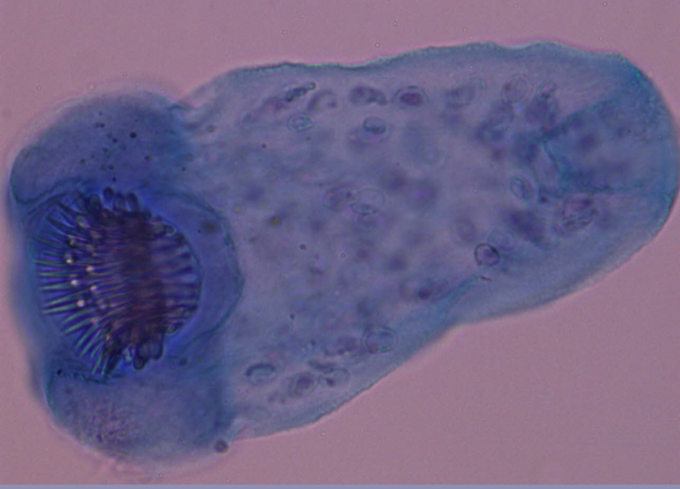

Echinococcus granulosus - Tasiemiec bąblowcowy - Wynicowany protoskoleks